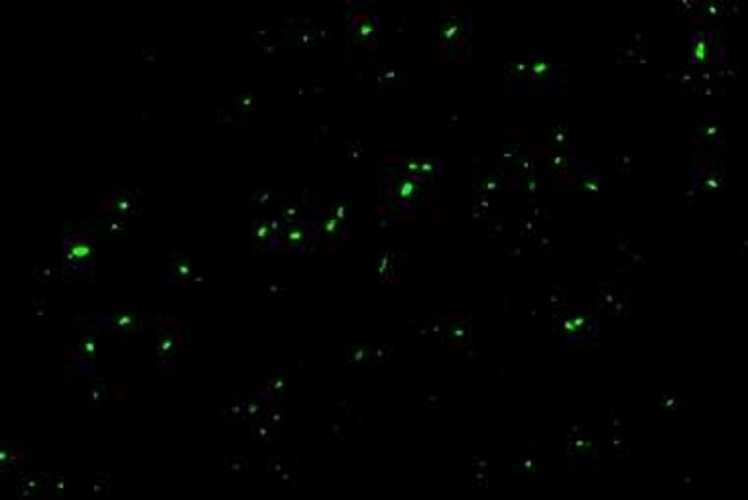

Cuando vio por primera vez las imágenes microscópicas de las manchas verdes fluorescentes que revelaban los micro-coágulos, lloró de alivio. Para ella, la confirmación de que tenía micro-coágulos supuso la validación de su enfermedad, «sobre todo después de no haberse hecho una prueba PCR al principio y de haber sido gaseada durante los últimos años».

A diferencia de los coágulos que obstruyen las arterias o las venas, los micro-coágulos se forman en los vasos sanguíneos pequeños cuando una proteína soluble llamada fibrinógeno se expone a moléculas que causan inflamación, las cuales pueden unirse al fibrinógeno y agregarse formando grumos pegajosos. «No son capaces de obstruir grandes vasos ni de causar síntomas potencialmente mortales», reconoce Putrino, pero señala que «pueden afectar significativamente a la función de los órganos».

Pretorius y sus colegas llevan más de una década estudiando tales micro-coágulos, y los han observado en pacientes con diabetes de tipo 2, síndrome de fatiga crónica, Alzheimer y enfermedad de Parkinson. En un estudio preliminar de 2021, observaron una formación sustancial de micro-coágulos en la sangre de pacientes con COVID-19 aguda, así como en personas con COVID larga que experimentan síntomas persistentes durante seis meses o más.

En el interior de los micro-coágulos persistentes, su equipo halló altos niveles de moléculas inflamatorias y una proteína llamada alfa-2-antiplasmina que impide su desintegración. Estas obstrucciones en los diminutos vasos sanguíneos de todo el cuerpo podrían dificultar el suministro de oxígeno y nutrientes a los órganos y tejidos, lo que podría provocar síntomas prolongados de COVID como fatiga, dolor muscular y niebla cerebral.